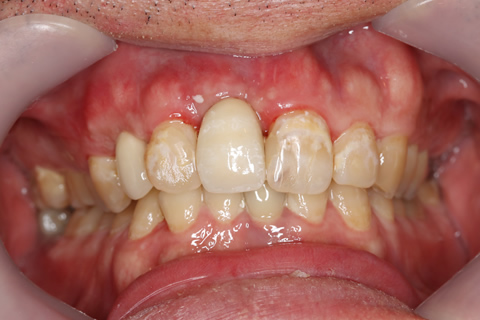

症例5

- 年齢・性別

- 35歳男性

- 治療期間

- 3ヶ月

- 抜歯

- 右上1.3左上6.7の残根抜歯

- 治療費

- 132万円

- 備考

- 右上1.3左上6.7の欠損部

- 治療内容

- 4本のインプラントを一回のオペで埋入。

- 施術の副作用(リスク)

- オペによる知覚障害。インプラントによる歯肉炎。インプラント脱落。